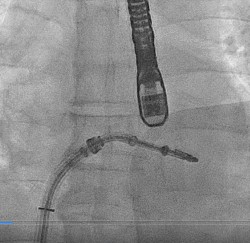

患者全麻以后,在经食道超声心动图和X射线引导下,经股静脉入路,将MitraClip瓣膜夹顺利送至二尖瓣前后叶交界中心处,成功捕捉二尖瓣前叶A2和后叶P2,经超声心动图反复确认瓣叶夹持牢固后,测定有效夹持长度10.4mm,评估反流量降至轻度,释放瓣膜夹,超声心动图评估瓣膜夹位置和功能良好,测定左房压降至26/12mmHg,再次评估反流量仍为轻度,手术顺利完成。

▲ 术前超声检查显示重度二尖瓣反流